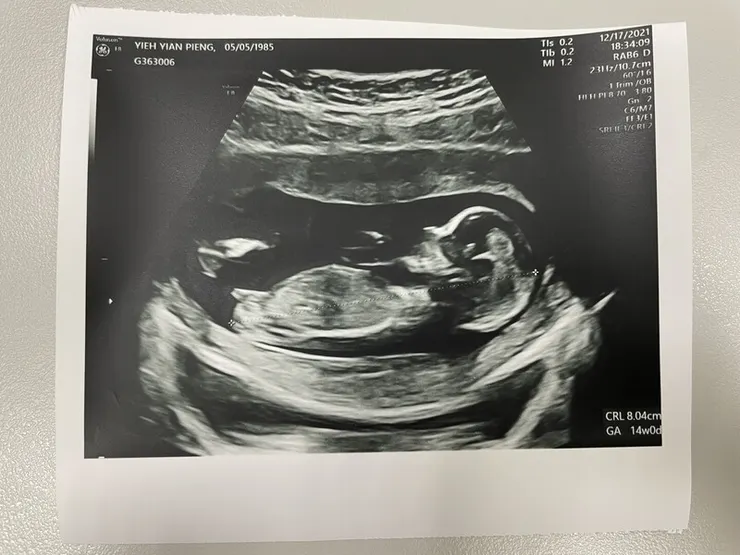

【第14周~鬆口好消息】

滿三個月後的第一次產檢~~~ 確認寶寶目前一切安好後,終於可以跟大家鬆口了!